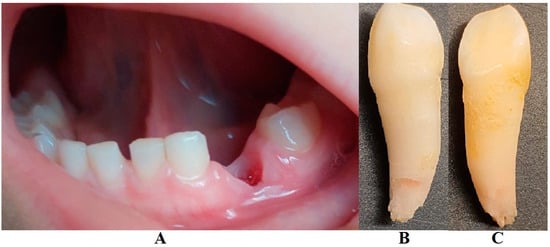

Figure 3.

(A)—Gingival inflammation, (B)—advanced tooth mobility, which led to the LPP diagnosis (details, in early August).

On the other hand, when the first Stage IV grade C localized periodontitis/LPP diagnosis was established (2 August), the clinical examination showed an increased mobility of the temporary lower left canine due to massive bone and periodontal ligament loss, associated with a localized inflammation of the free gingival margin around the tooth, and with small amounts of dental plaque due to difficulties with oral hygiene (Figure 2 and Figure 3). No other plaque deposits, inflamed gingiva, or teeth mobility issues were detected during the clinical examination. When this information was correlated with the radiological examination from two months prior (19 June, Figure 1), with localized bone loss, the diagnosis based on clinical and radiological data was confirmed, with no need for further radiological examination. Moreover, the blood test with higher levels of lymphocytes [2,14] also confirmed Stage IV grade C localized periodontitis/LPP diagnosis. To assess the periodontal pocket bacteria responsible for this atypical LPP case (i.e., temporary molars/incisors are usually involved [1,2,10], rather than the canine, as in this case), a canine periodontal sulcus secretion test was sampled and sent to the laboratory.

A rapid Stage IV grade C localized periodontitis/LPP diagnosis is essential, since the aggressive auto-immune response to bacteria can rapidly lead to a resorptive process [1,2,3,4,5,6,7,8,9,11]. Thus, a simple bacterial test to identify the pathogenic bacterium types would provide both diagnostic confirmation and justification for antibiotic treatment [2,3,11,12,13,14,15]. If LPP disorder is identified early, there is time to wait (i.e., usually up to two weeks) for lab test results, and only then should antibiotic therapy proceed [5,6,9,10,16,17,18]. However, if the LPP diagnosis is late (as it was herein), antibiotic treatment must be started, with a combination of two large-spectrum antibiotics (amoxicillin and metronidazole) to cover most bacterial types [5,6,9,10,16,17,18]. It must be emphasized that LPP usually comes without or with very few plaque deposits (as the case herein showed—see Figure 1, Figure 2, Figure 3 and Figure 4), with little influence over surrounding gingival inflammation [1,2,4,5,6,7,8,9,10].